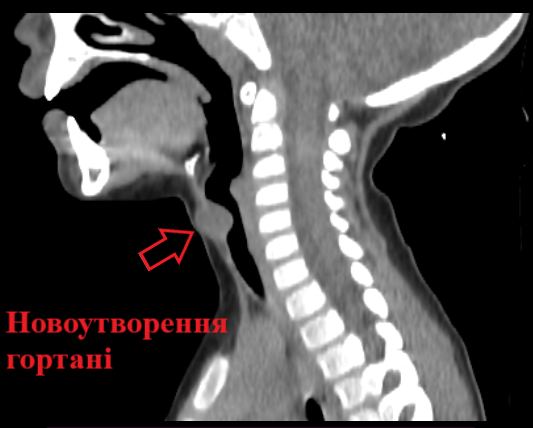

Мальчик стоял на учете у отоларинголога с диагнозом "увеличенные аденоиды". Однако, когда ребенка положили в больницу, ему провели фиброэндоскопию, а также МРТ с контрастом. В результате оказалось, что аденоиды у малыша нормального размера. Вместо этого у него в гортани обнаружили новообразование (мукоцеле подскладочного пространства), которое перекрывало практически 80% дыхания.

Тщательное исследование позволило успешно провести операцию по удалению доброкачественной опухоли гнойного характера. На такой шаг доктора пошли из-за того, что образование могло в любой момент увеличиться и лишить мальчика возможности дышать. Это достаточно редкая операция и хирурги провели около 3 часов в операционной.